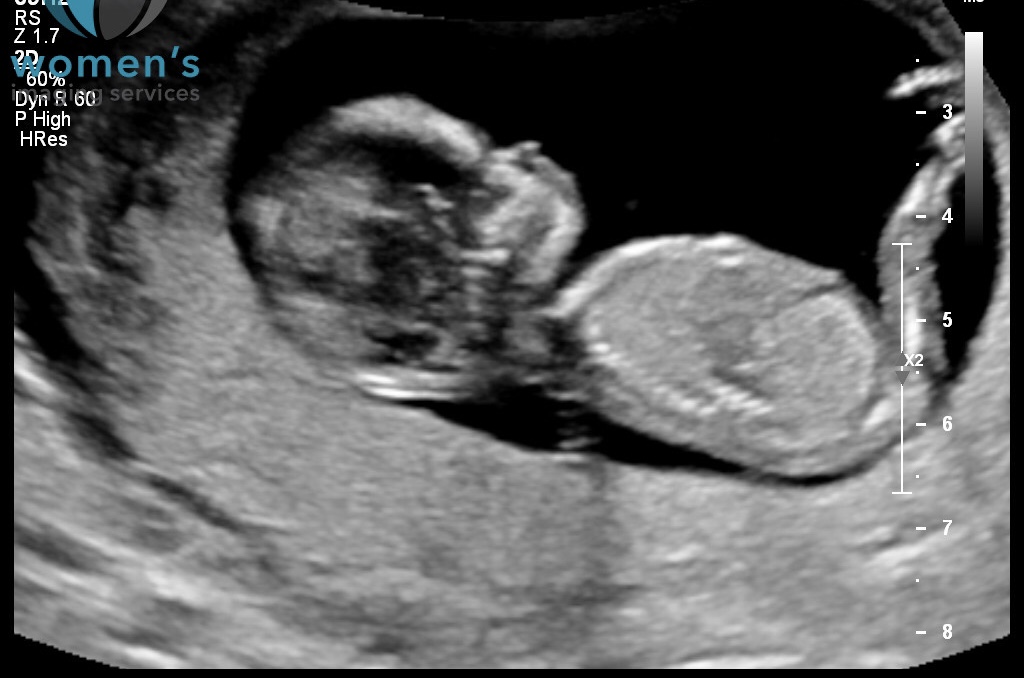

just wondering if anyone can see whether this is a girl or boy was recommended by someone to use this forum.

Praying for a girl, have two healthy boys already.

I don't see any nub here -- looks like leg is perfectly obscuring it. But girly skull, for what it's worth ;)